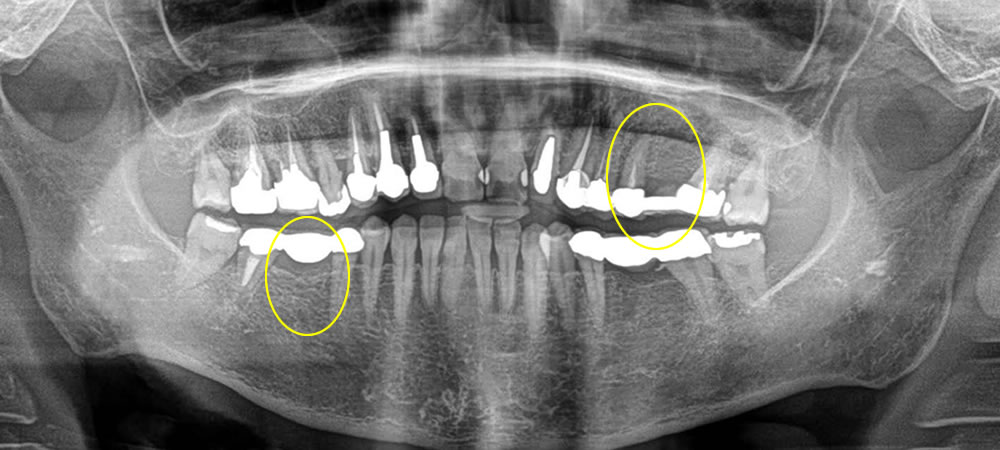

痛みのあるブリッジの歯をインプラントで治療した症例

こちらの患者さまは左上のブリッジ治療を行っている歯が痛いとの事で来院されました。左上はブリッジのつけてある歯が1本割れてしまっていたので、その歯を抜いて治療していく事になりました。

まずブリッジを除去し、残す事のできない歯を抜き、元々歯のない部位と歯を抜いた部位にインプラント治療を行いました。歯を抜き、即時でインプラントを入れる部位には埋入と同時に骨を作る処置(骨造成)を行い、特殊な縫合で傷口を閉鎖し、歯茎の形態も同時に調整していきました。

次に右下のブリッジの入っている部位もインプラントに変えていきたいとの希望により、ブリッジを除去し歯の無い部位にインプラントを埋入しました。